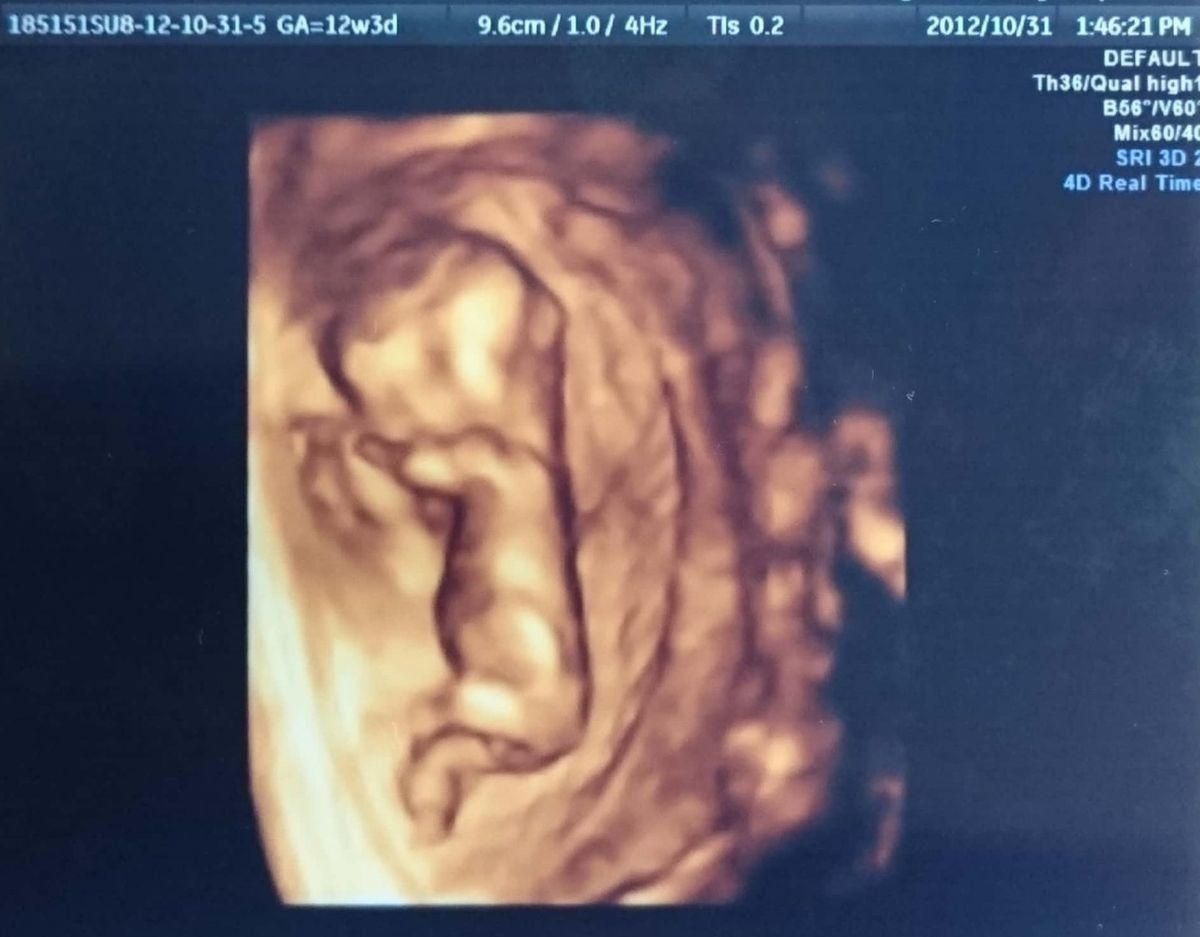

妊娠12週のエコー写真 初めての3D写真のリアルさにビックリ!

9.6cm(3Dのエコー写真では何を測ったかの情報記載がないため、「9.6cm」という数字が何を表しているのかは不明。)

最初に通っていた病院はお産ができるところでなかったため、紹介状を書いてもらって転院。このエコー写真の1週間前に転院先で初検査をしましたが、その時に絨毛膜下血腫と言われ、自宅で安静の指示が…。とはいえ、その翌週となった今回の検査では、3Dで元気そうな胎児を確認できました。安静の指示はこの後、1ヶ月続きました。